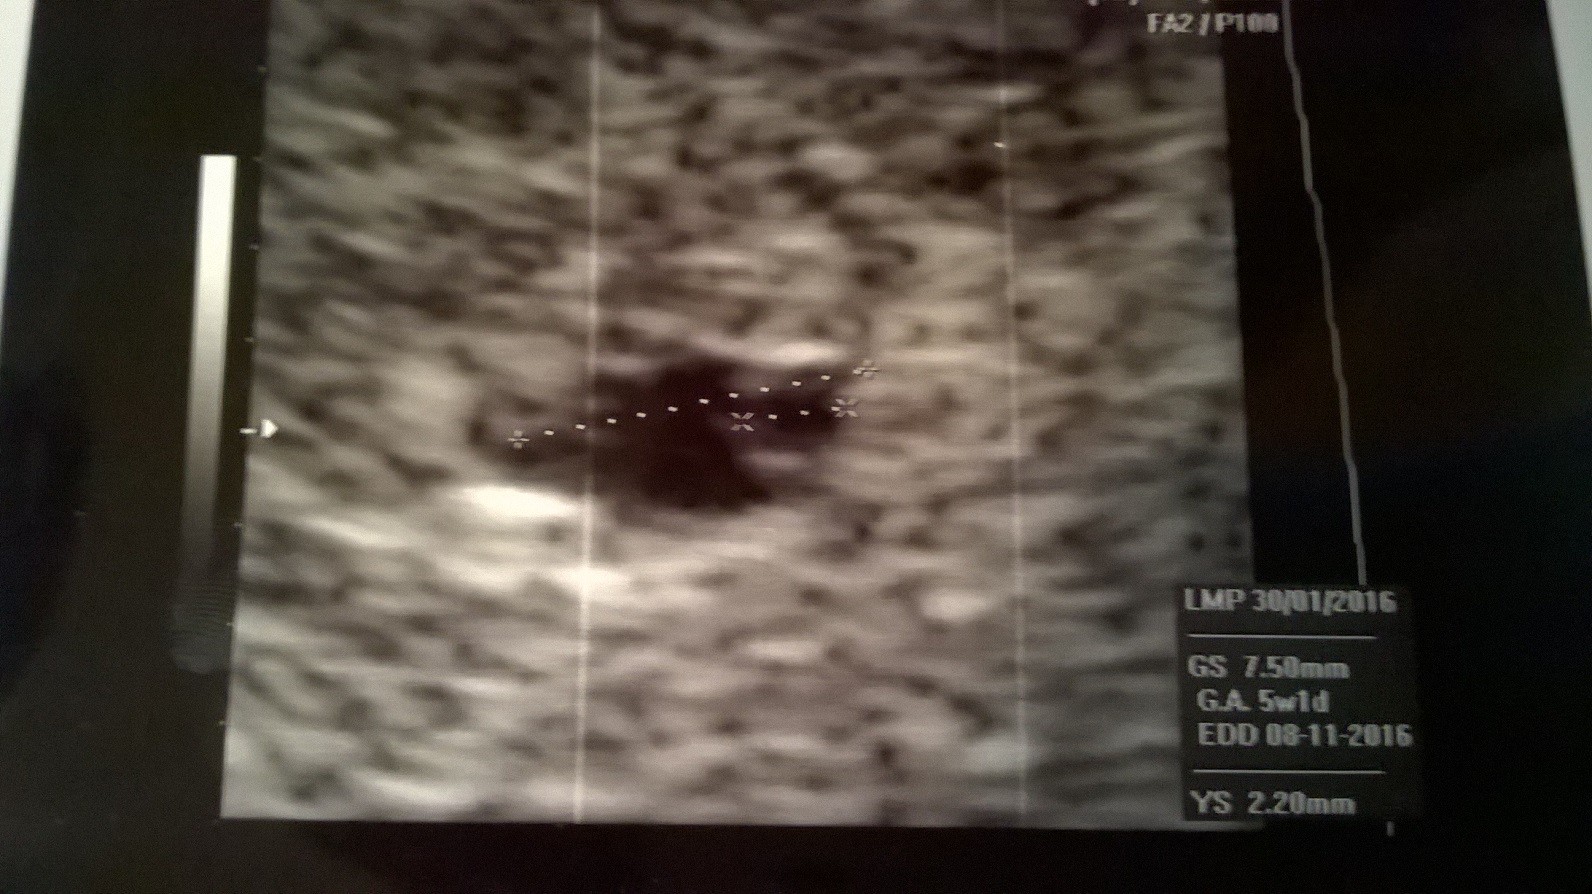

WP_20160309_001.jpg

Powiedziała, że za 2 tygodnie zobaczymy, mam się oszczędzać, nie dzwigać, nie biegać po schodach, bo ja dzisiaj biegałam kilka razy na 3 piętro - wiem jestem idiotką. Zero sexu

• WP_20160309_001.jpg

391,7 KB · Wyświetleń: 139